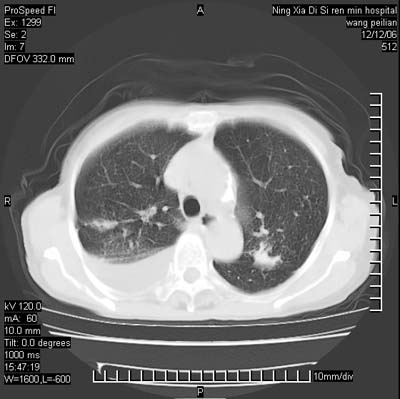

标题: CT5609:胸部:女77 病史不详 [打印本页]

标题: CT5609:胸部:女77 病史不详

两肺可见多个大小不等的结节,左侧有胸水,纵隔淋巴结增大,考虑是细支气管肺泡癌

两肺尖纤维索状影,两下肺结节块状影,且有钙化灶,右胸腔积液。考虑肺结核并胸膜炎。

双侧肺结核伴右侧胸腔积液.

两肺尖纤维索状影,两下肺结节块状影,且有钙化灶,右胸腔积液。考虑肺结核并胸膜炎肺间质纤维化

从图中见许多致密的结节影,,增强后明显强化,考虑血管炎症肉芽肿.当然还有慢支并小叶中央型肺气肿以及陈旧结核,胸腔积液.

考虑:1、慢性支气管炎合并全小叶型肺气肿、间质纤维化;

2、双肺结核;

3、右侧胸膜炎(积液)。

1、双肺继发型肺结核(以纤维、增殖灶为主);

2、右侧胸腔积液;

3、其余符合老年肺改变。

双肺见多个结节状及条索状影,双侧胸腔积液,右侧叶间积液,考虑结核性胸膜炎